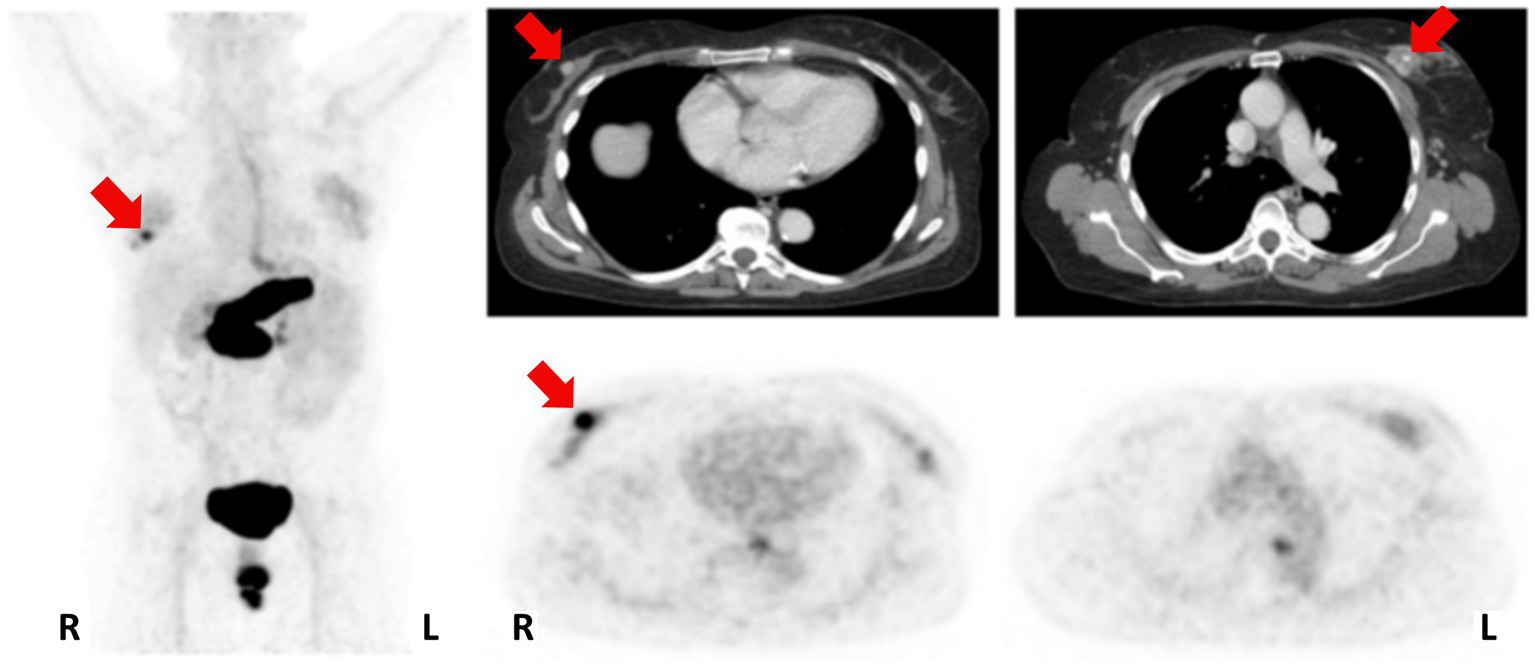

In 2016, [68Ga]Ga-RM2 (Figure 6, 8) was used for pre-treatment staging by PET/CT imaging of patients with primary BC, as shown in Figure 9. The study revealed a low to moderate uptake of the tracer in normal breast tissue, while the tumor uptake correlated well with ER/PR expression, HER2 status and MIB-1 proliferation index. A strongly increased uptake of the tracer was observed in 13 of the 18 tumors analyzed and all the PET-positive tumors stained positively also for ER and PR. Importantly, high [68Ga]Ga-RM2 uptake was detected also in lymph nodes and bone metastasis, confirming that ER expression is a good predictor for GRPR expression quantification by [68Ga]Ga-RM2 PET (89).

Figure 9

Patient with an ER/PR-positive tumor in the right breast (PET-positive; SUVmax 8.32) and an ER/PR-negative tumor on the left side (PET-negative; SUVmax 2.68). MIP left; CT upper row; [68Ga]Ga-RM2-PET lower row; primary tumors indicated by red arrows. Reprinted from Gastrin-releasing Peptide Receptor Imaging in Breast Cancer Using the Receptor Antagonist 68Ga-RM2 and PET by Stoykow et al. (89), under Creative Commons Attribution (CC BY-NC) license.